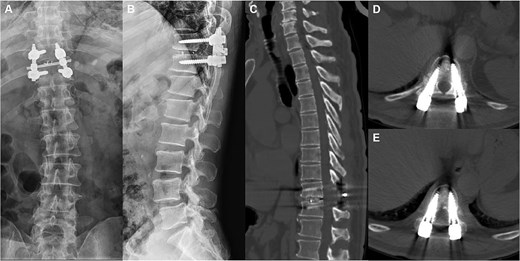

A 66-year-old male presented with a 1-year history of progressive low back pain and bilateral lower limb numbness, intensifying over the preceding month. Symptoms began insidiously without trauma and progressively worsened with prolonged standing and walking, improving with rest. The patient described deep, aching pain that significantly impacted his daily activities. Physical examination revealed bilateral lower limb numbness, especially prominent in the anterior thighs, an unsteady gait with a broad-based stance, decreased quadriceps muscle strength, reduced sensation below the navel extending to the groin, and positive bilateral Babinski signs indicating upper motor neuron involvement. Initial external X-rays suggested only L4 vertebral displacement, inconsistent with the clinical findings, prompting hospital admission for further evaluation. Refined imaging studies revealed previously unrecognized pathology. X-ray (Fig. 1A) and CT (Fig. 1B–D) demonstrated concomitant T10 vertebral body slippage, while MRI (Fig. 1E) showed severe T10/11 spinal cord compression with associated signal changes. The patient was diagnosed with thoracic spinal stenosis due to T10–T11 vertebral slip, explaining the bilateral lower extremity neurological symptoms and gait instability. Given the prolonged symptom duration, recurrent nature, and functional impact, surgical intervention was indicated after multidisciplinary discussion. The patient underwent T10–T11 thoracic interbody fusion with comprehensive decompression under general anesthesia. The procedure included herniated disc material removal, extensive posterior decompression, precise pedicle screw and titanium rod placement for stabilization, and autologous iliac crest bone grafting for interbody fusion. Postoperative management included comprehensive pain control and neurological monitoring. Follow-up X-ray (Fig. 2A and B) and CT (Fig. 2C–E) demonstrated successful vertebral realignment with the internal fixation in the ideal position. By postoperative Day 6, the patient reported significant back pain and leg numbness relief. Progressive improvement with structured physical therapy led to discharge on Day 10. One-year follow-up examination (Fig. 3) revealed stable fixation with continued symptom resolution, enabling free ambulation and complete return to normal activities.

Postoperative follow-up images. (A–D) Repeat CT plain and 3D reconstruction at 6 months postoperatively showed ideal position of the T10–11 internal fixation and fusion device, straight posterior margin of the vertebral body, and no obvious signs of compression of the dural sac. (E, F) Review X-ray at 1 year postoperatively showed that the internal fixation device was in place without obvious dislocation, and the vertebral body slippage was satisfactorily repositioned.